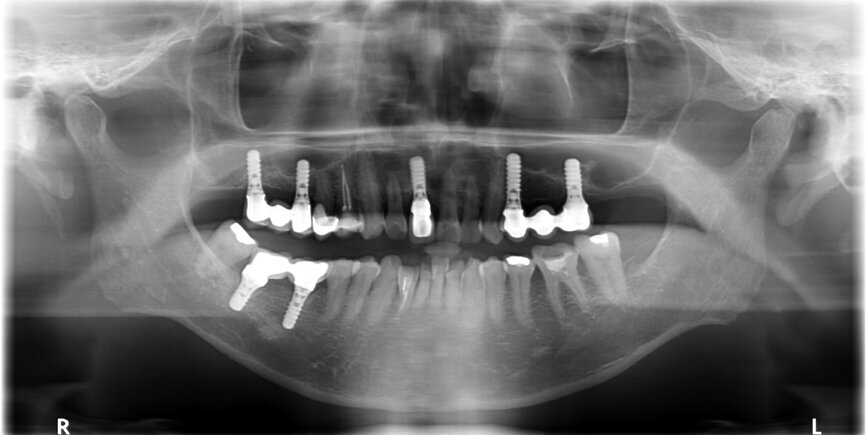

After careful assessment of the patient’s anatomical condition through a panoramic radiograph and CBCT scan (Figs. 1–3), it was possible to verify ideal interradicular bone availability, allowing the following treatment plan:

Fig. 2: Panoramic radiograph.

Fig. 3: Tooth #36 initial situation.